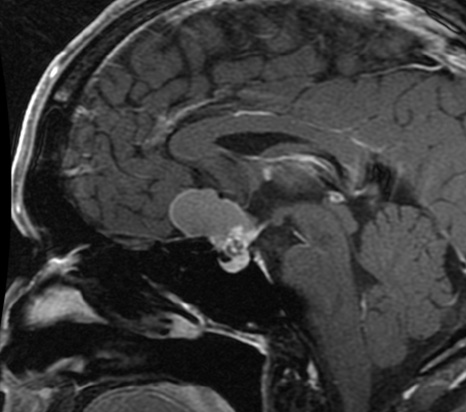

【ラトケ嚢胞】

非腫瘍性病変であり、下垂体の中にもともと存在する袋が拡大したものです。

30~60歳代に多い病気です。

無症状であれば基本的には経過観察を行いますが、大きくなり色々な症状が出現しているときには嚢胞の開放術を推奨致します。

ほとんどは経蝶形骨洞手術で改善します。